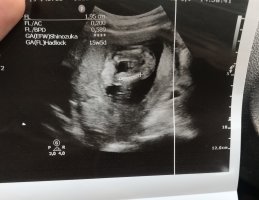

@Zerre tam çekememişsin şu apış arasındaki çıkıntıyı çekip atsana bana göre kız mrk ettim bi daha sadece o bölümü çekip atabilir misin kız harici bişi çıksın saçlarımı yolarım

Benm kendi doktorum olmadğı içn 12. hftada farklı bir doktora ikili test yaptrmştm ve cinsiyetinin kız olduğunu söylemşti

ama 16. haftada tekrar gittiğimde kendi doktorum erkek olduğunu söyledi sizce nedir? doğru sonuç için detaylıyı mı beklemeliyim???

Belittiğiniz haftalarda cinsiyet tahmininde yanılmalar olabilir. Gebeliğin 17-18-20 . haftalarında bebeğinizin cinsiyetini net olarak öğrenebilirsiniz.